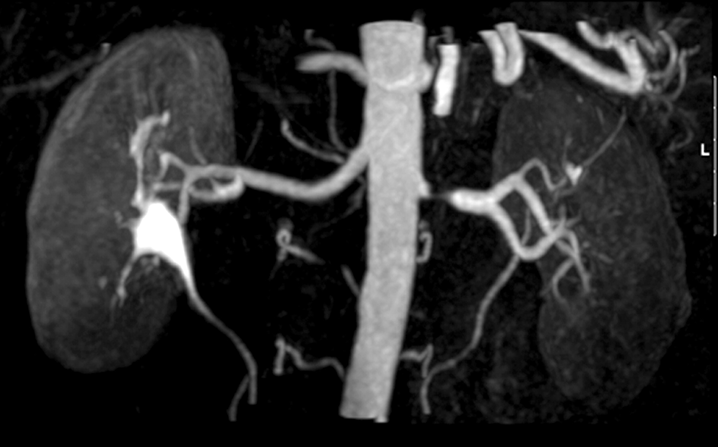

What is this?

Renal artery stenosis